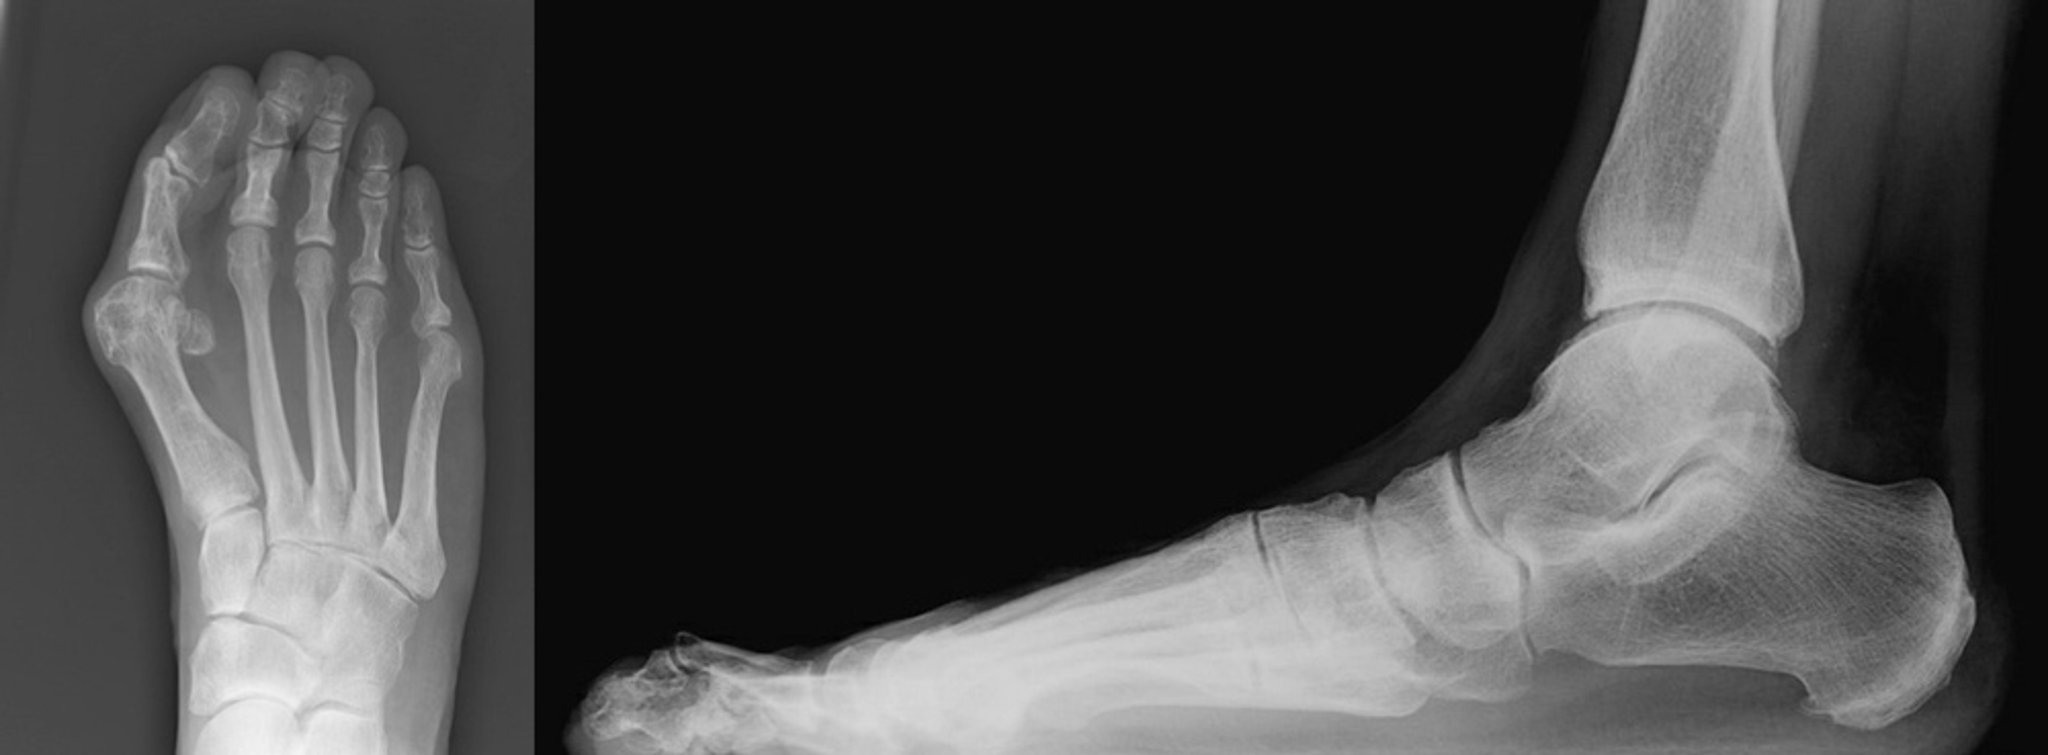

Röntgenaufnahmen vom Ballenzeh mit Hammerzehen

Gezeigt werden anteroposteriore und laterale Ansichten eines Ballenzehs mit einer Hammerzehe der zweiten Zehe. Die anteroposteriore Ansicht zeigt einen schweren Hallux valgus mit medialer Abweichung des ersten Metatarsalknochens. Der Hallux liegt an der zweiten Zehe an. Der zweite Finger ist seitlich abgewinkelt mit Verengung des zweiten Metatarsophalangealgelenks (links). Die Seitenansicht zeigt, dass der zweite Zeh am Metatarsophalangealgelenk disloziert ist. Es gibt eine Hyperflexion am proximalen Interphalangealgelenk mit Überstreckung des distalen Interphalangealgelenks der zweiten Zehe (rechts).

Images courtesy of James C. Connors, DPM.